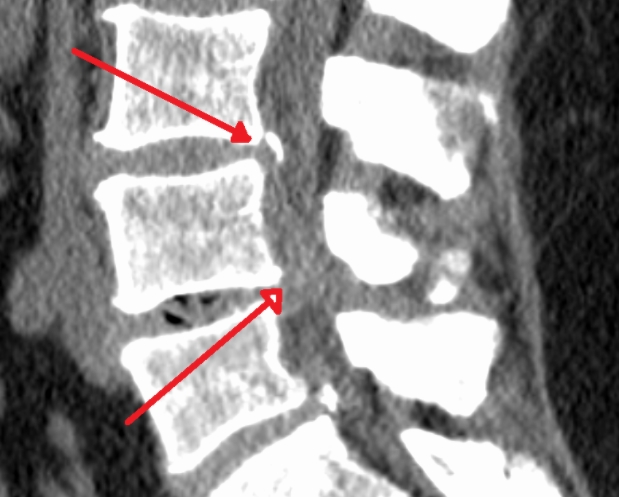

그 허리통증 원인을 특정할 수 있고 많이 알려진 허리 질환인 요추추간판헤르니아가 바로 허리 디스크 입니다. 척추뼈 사이에 있는 추간판이 망가져서 그 안에 있는 젤라틴 같은 디스크가 탈출되어 신경을 압박하면서 통증이 나타납니다.

추간판 이라 불리는 곳은 수분이 많이 함유된 젤리 모양의 수핵과 그것을 둘러싸고 있는 연골조직으로 이루어져 있습니다. 이들은 요추에 가해지는 압력을 분산시켜 충격을 완화해주는 쿠션 역할을 해 주고 있습니다. 그런데 연골조직이 탄력을 잃고 작은 균열이 생기면서 수핵의 일부가 밖으로 탈출하게 됩니다. 그래서 허리 디스크 질환을 추간판 탈출증이라고 합니다.

밖으로 밀려난 수핵이 신경을 압박해서 허리 통증이 생기는데 이 상태를 방치하게 되면 수핵이 점점 더 밖으로 밀려나와 통증과 저리는 증상이 심해집니다. 허리 디스크와 협착증의 차이 중 눈에 보이지는 않지만 발생 원인과 연령대가 다르다는 점이 가장 크다고 할 수 있습니다.